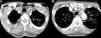

Case ReportOur patient was a 65-year-old woman with a history of bronchial asthma, with bronchiectasis, and PsA with mixed erosive involvement; she was negative for HLA-B27. She had received methotrexate and leflunomide from 2011 until 2013, when they were interrupted because of remission. She was presented with a 2-month history of fever and weakness, but did not report headaches, vision disorders or chest, abdominal or limb pain. Physical examination revealed only a difference in arterial blood pressure of 20mmHg and that some pulse rates were lower in left limbs. The temporal arteries were not tender on palpation, and the pulse rate was normal and symmetric. Laboratory tests showed a hemoglobin concentration of 9.9g/dL (normal: 12.0–15.0), erythrocyte sedimentation rate of 102mm/h (0–20), C-reactive protein 140.90mg/L (<5mg/L) and iron 11μg/dL (35.0–145.0). The remaining parameters were normal (thyroid-stimulating hormone, creatine phosphokinase, Mantoux test, tumor markers, protein profile, serological tests, immunological tests, urinary sediment and cultures). Chest radiography, echocardiogram, gastroscopy with duodenal biopsy and colonoscopy were normal. Chest and abdominal computed tomography (CT) showed stable bronchiectasis and thickening of the abdominal aortic wall, indicative of aortitis. Computed tomography angiography (CTA) (Fig. 1) also showed evidence of concentric inflammatory thickening of the supra-aortic trunks and aortic arch. Temporal artery biopsy was performed with the histological confirmation of GCA. Treatment was begun with corticoids at a tapering dose starting with 2mg/kg/day and methotrexate at 15mg/weekly, and the symptoms disappeared.

Computed tomography angiography: the presence of a concentric inflammatory thickening/vasculitis of all the supra-aortic branches (A) and of the aortic arch (B) is confirmed (arrows). The greatest involvement appears to be that observed in left subclavian artery, and there is no evidence of significant stenosis at any point. In the carotid territory, only the common carotid artery is affected, there being no extension to internal carotid artery.